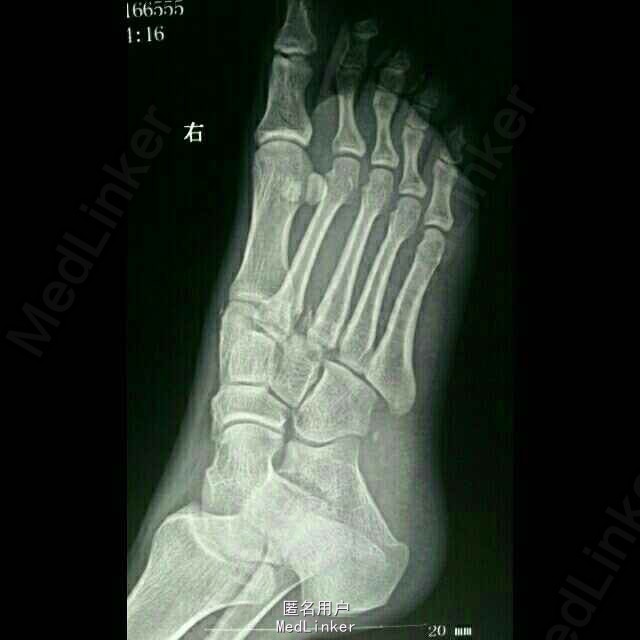

患者青年男性,28岁,负重下楼时扭伤右足1天。右足肿胀痛,活动受限,不能行走。

足背肿胀、青紫,第2—3跖骨基底部压痛阳性,足背动脉搏动弱,各趾未见明显异常。 CT示:右足第2、3跖骨基底部骨折,内侧楔骨、骰骨骨皮质撕脱骨折

诊断:1.右足第2、3跖骨基底部骨折(Lisfranc损失) 2.右足内侧楔骨骨折 3.骰骨骨折 治疗:切开复位内固定